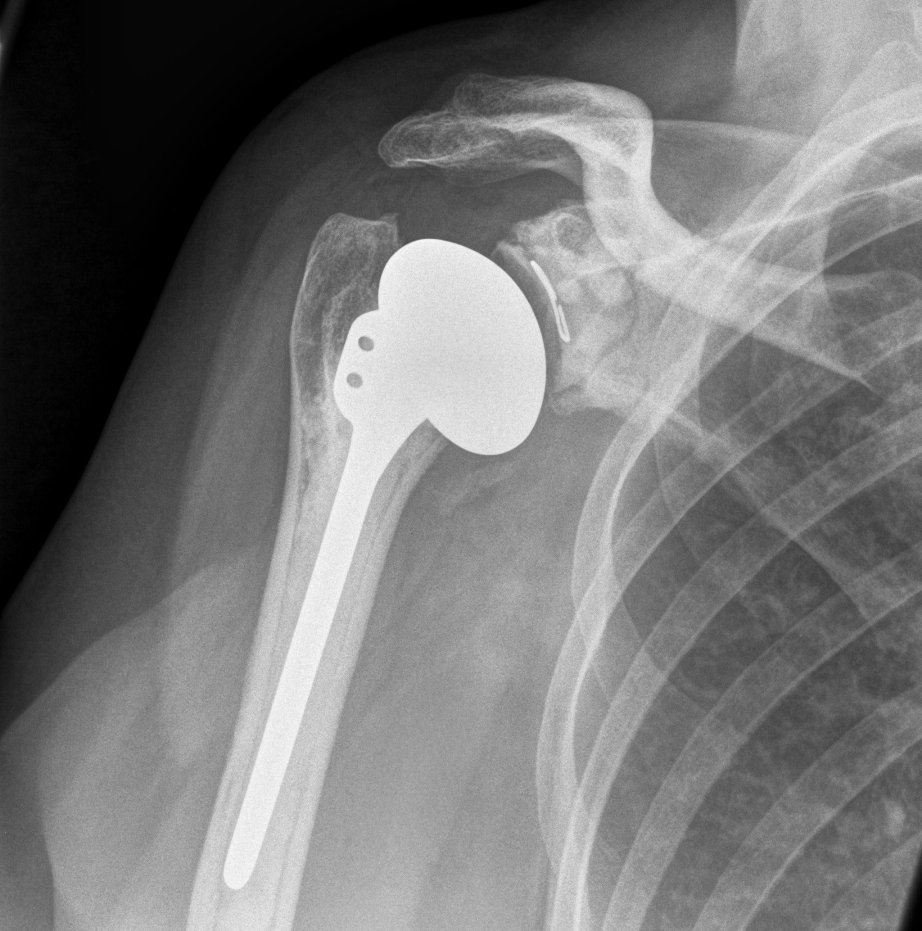

Anatomical Total Shoulder Design

Stem

Stemmed versus short stems versus stemless

Australian Joint Registry 2024

- 12,000 aTSA for OA

- 10 year revision rate stemmed 13%

- 10 year revision rate stemless 14%

Fixation

Glenoid design

Cemented all poly versus uncemented metal back glenoid

Significantly higher revision rate will metal verus poly glenoids

- Australian Joint Registry

- 11,000 aTSA at 5 years follow up

- revision rate cemented glenoid 3.7%

- revision rate uncemented 17.9%